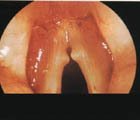

喉鏡檢查可見聲帶游離緣前中部表面光滑、半透明帶蒂或不帶蒂的新生物。息肉多成灰白色或淡紅色,偶有紫紅色,常呈綠豆黃豆大小。聲帶息肉一般單側多見,亦可兩側同時發生。帶蒂的聲帶息肉可隨呼吸氣流上下活動,有時隱匿於聲門下腔,檢查時容易忽略。喉動態鏡下可見聲帶周期性差,對稱性、振幅、黏膜波減弱或消失,振動關閉相減弱。